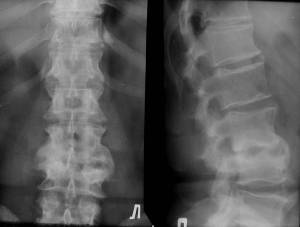

На рентгенограмах до цього часу визначається зменшення висоти або повна відсутність міжхребцевого диска, руйнування прилеглого до цього диску ділянки тіла одного або частіше двох суміжних хребців. Уражаються практично завжди, як і при туберкульозі, тіла хребців. При аналізі структури тел уражених хребців можна відзначити виражений остеосклероз, що дозволяє запідозрити нетуберкульозних природу захворювання (рис.8).

Мал. 8. Хронічний кокковую спондиліт. Контактна деструкція в тілах 2 і 3 поперекових хребців, в суміжних ділянках тіл уражених хребців - дифузний остеосклероз. Висота диска різко зменшена, але проміжок між тілами збережений завдяки потужним підзв'язкового окостеніння по бічних і передньої поверхонь сегмента.